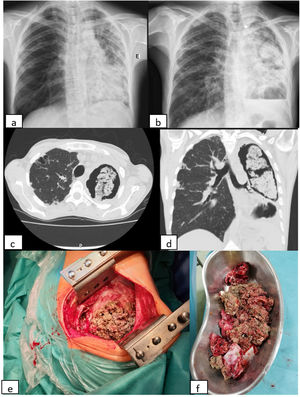

We report the case of a 44-year-old woman with bronchiectasis due to whooping cough in childhood. She was referred to an autoimmune diseases consultation due to a lower limb vasculitis, whose study was negative except for anti-neutrophil cytoplasmic antibodies (ANCAs – atypical pattern) of 1/160. She started steroid therapy in considerable doses in order to control her disease. Chest X-rays demonstrated evolution of previous lung lesions to aspergilloma and a six-month course of itraconazole was prescribed. Despite that, clear worsening of the lesions with complete destruction of the left lung was perceived and the patient was proposed for left pneumectomy. At the surgery, filling of the left pleural cavity with brown necrotic material was observed. Histological exam of the surgical fragments revealed one re-epithelized cavitated lesion associated with fungal structures of the Aspergillus type. The microbiology of the surgical specimen identified Aspergillus fumigatus. Patient status after surgery has improved (Fig. 1).

(a, b) X-ray evolution of the patient. The X-ray on the left (a) was performed before corticosteroids therapy and the one on the right (b) about seven months after the beginning of that therapy; (c, d) coronal and axial views of thoracic computed tomography performed after six months of Itraconazole, showing giant aspergilloma in left lung; (e, f) necrotic material of fungus ball observed during surgery.